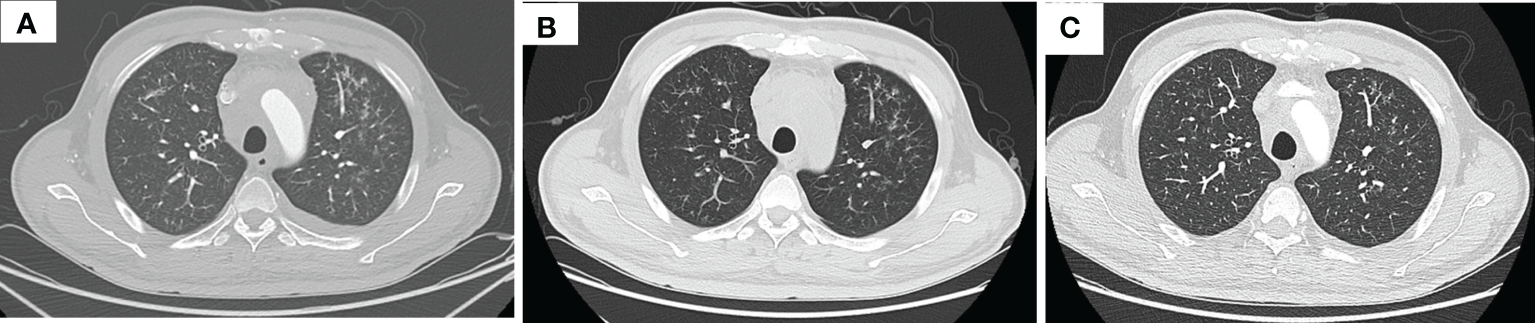

Figure 1

Thorax CT imaging of the patient before and after treatment of tislelizumab plus albumin-bound paclitaxel. (A–D) show the CT imaging at baseline, the end of the second cycle, the third cycle, and the fifth cycle, respectively. (A) Baseline imaging on 19 May 2020; (B) imaging on 16 July 2020, after two cycles treatment; (C) imaging on 9 September 2020, after three cycles treatment; (D) imaging on 3 November 2020, after five cycles treatment.

After three times treatment by linear accelerator radiotherapy, the aforementioned symptoms significantly worsened. He got better after drainage of pleural effusion and discontinued radiotherapy. Then, he was treated with tislelizumab (200 mg D1, 21 days a cycle) plus albumin-bound paclitaxel (200 mg D1, 100 mg D8, 21 days a cycle) for five cycles from 11 June 2020 to 10 October 2020. The symptoms improved further since the fifth day after immunochemotherapy. The patient was assessed as having stable disease (SD) at the end of the second cycle treatment (Figures 1B–D). The response was assessed as SD at the end of the fifth cycle with the lesions in mediastinum shrinking successively. However, the patient was indicated with pulmonary fibrosis, which might be grade 1 checkpoint inhibitor pneumonitis (CIP) (Figures 2A, B), grade 2 leukopenia, and grade 3 thrombocytopenia. The CIP was closely monitored and got better when assessed on 22 July 2020 (Figures 2B, C). The hematological toxicities recovered after symptomatic treatment.